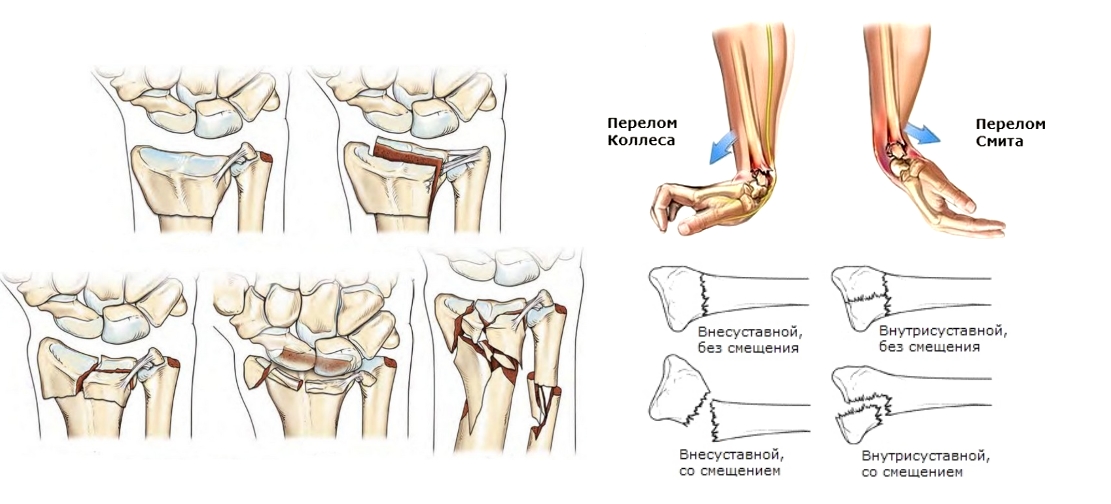

Классификация переломов запястья основывается на наличии или отсутствии смещения сломанных участков кости относительно друг друга. Важно также учитывать, затрагивает ли повреждение сустав. Например, внутрисуставной перелом лучезапястного сустава может привести к длительной иммобилизации и потере подвижности.

Травматологи выделяют оскольчатый перелом, который характеризуется разделением кости на три или более фрагмента. Разнообразие типов повреждений создает уникальный набор симптомов, которые могут проявляться по-разному: у одних пациентов они могут быть слабо выражены, у других – вызывать ярко выраженные клинические проявления. Общие признаки перелома запястья включают: